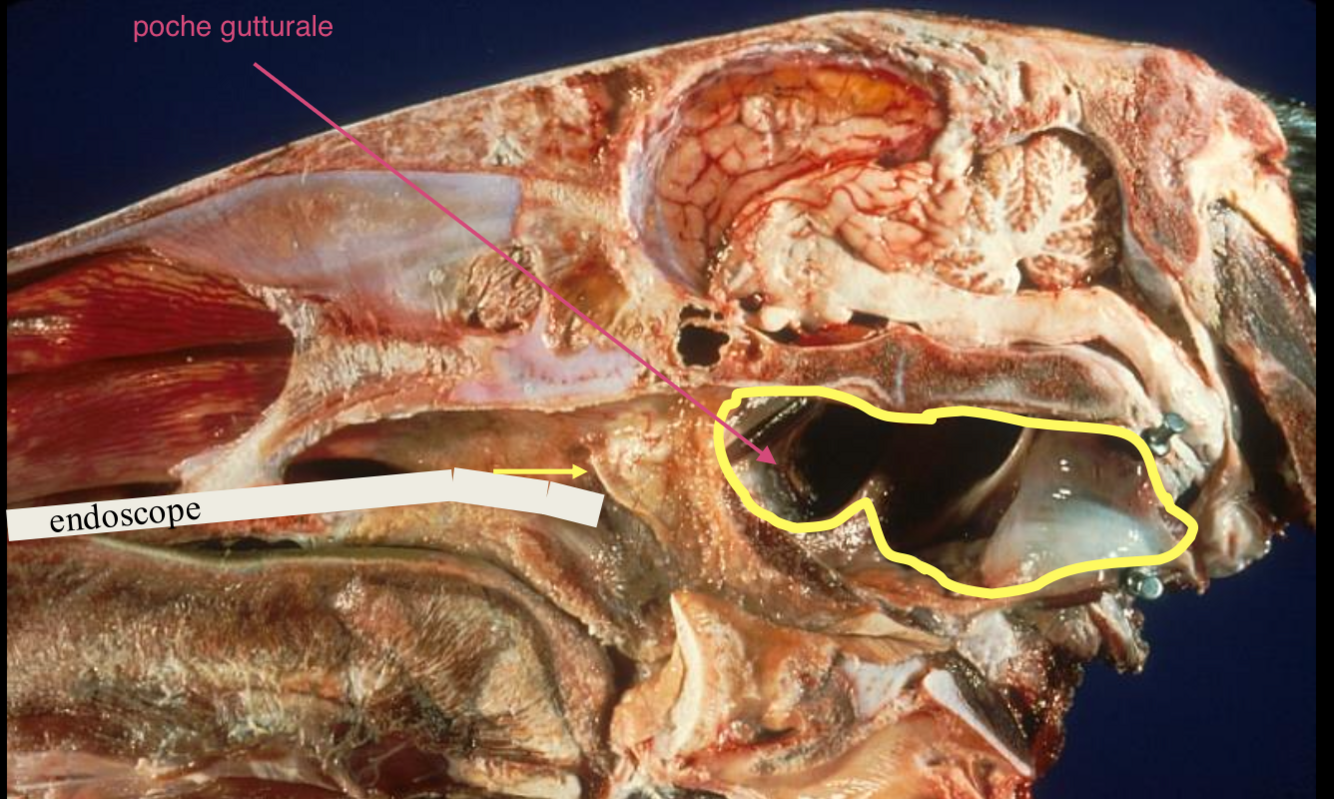

Anatomie de la poche gutturale

Diverticule de la trompe d’eustache

- os styloide qui coupe la poche en 2 (medial et latéral)

quelles sont les artères importantes qui passent dans la poche gutturale (3) Dans quel compartiment?

a. carotide interne,

a. maxillaire

-> dans le compartiment latéral